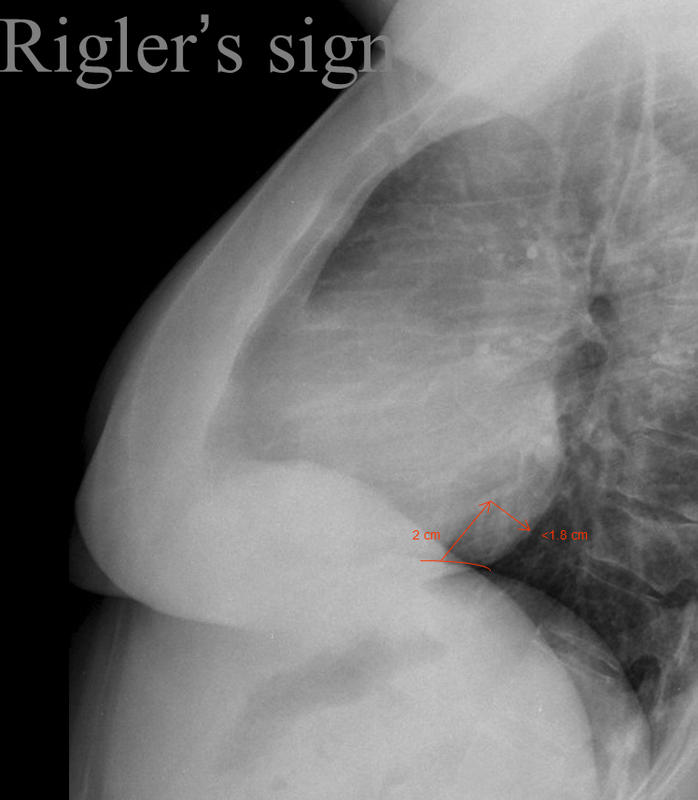

Gallery Signs Rigler's sign to assess LV size

Rigler's sign

to assess LV size